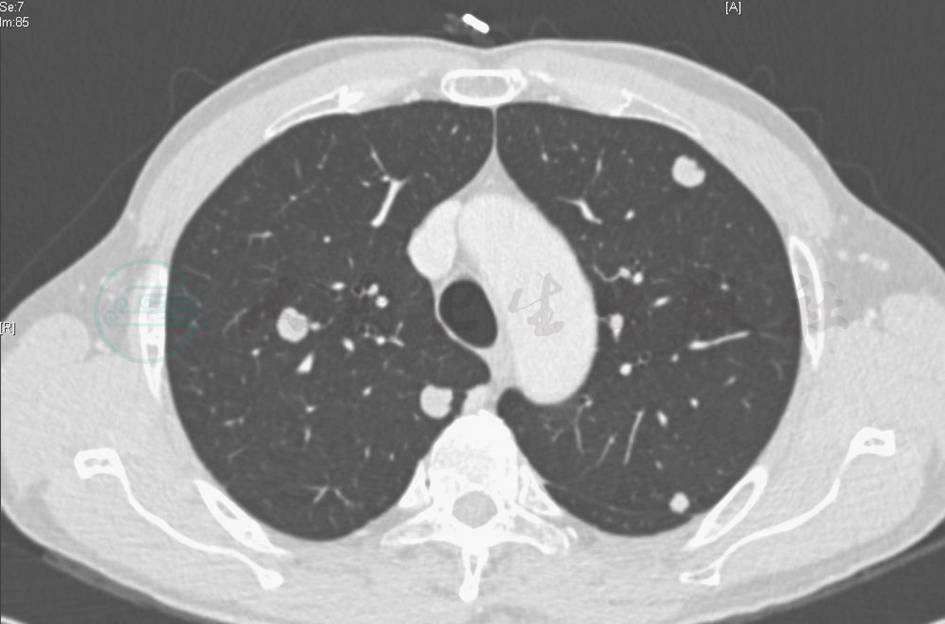

胸部CT:双肺多发高密度实变影,病灶以双肺中下为主(图11)。

图11 入院后复查CT表现

明确诊断后,考虑到患者双肺多发病变,无手术指征,采取停用前述抗感染药物,给予甲泼尼龙,患者未再发热,咳嗽、咳痰、胸痛症状缓解,但复查胸部CT仍显示病变进一步发展(图13)。

图13 激素治疗18天后复查胸部CT表现

胸部CT可见双肺病灶进一步增多,以结节和团块状实变为主